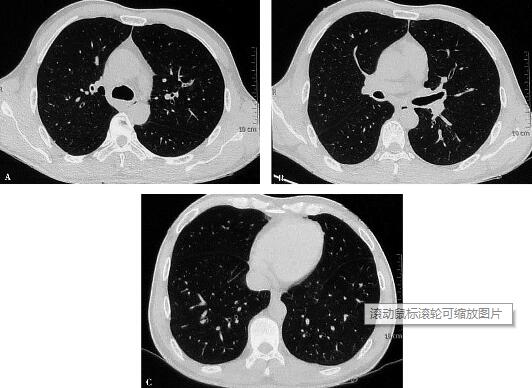

①血常规:白细胞计数17.48×109/L,嗜酸性粒细胞计数6.68×109/L,百分比38.2%。②动脉血气分析:pH 7.447,PaO2 84.8mmHg,PaCO2 46.6mmHg,HCO-3 30.2mmol/L。③肺功能:肺通气功能、小气道功能、弥散功能均正常,支气管激发试验阳性。④胸部CT:双肺散在纤维索条影(图2)。⑤血液生化检查:血清IgE及真菌抗原检测均正常,过敏原检测和粪便中寄生虫卵、潜血检查均阴性,风湿病抗体和抗中性粒细胞抗体均阴性。⑥PPD试验,结果为14mm×15mm。

图2

①患者抗感染治疗前后血常规白细胞总数、嗜酸性细胞计数和比例均升高,提示既往抗感染治疗无效;②肺功能及血气分析未见异常,虽然支气管激发试验阳性,但因病史不典型且嗜酸性粒细胞增高原因不明确,只能说明存在气道高反应;③患者否认不洁饮食史,无疫区旅行史及无宠物饲养史,消化道症状轻微,近期恶心,无腹痛腹泻,粪便寄生虫卵、潜血检测阴性,尽管与儿子具有相同的病情,但目前无充分的寄生虫感染证据;④既往无变态反应性疾病病史(如荨麻疹、过敏性鼻炎、药物过敏史等),无风湿性疾病相关疾病的症状和体征,风湿病相关抗体阴性,血清IgE正常,因此无明确变态反应性疾病、血管炎的证据;⑤胸部CT示双肺纤维索条影,未见斑片浸润影,影像学不符合嗜酸性粒细胞增多伴肺浸润的表现;⑥PPD试验,结果(++),结合胸部CT表现,不支持肺结核的诊断;⑦患者无免疫功能低下基础,无系统症状,真菌抗原阴性,无确切真菌感染证据。